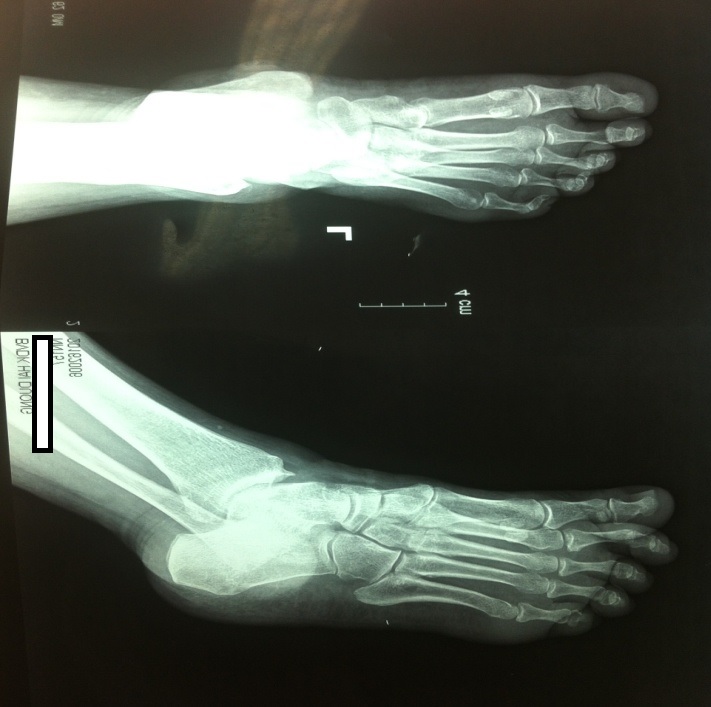

7. Chụp x quang xương bàn chân và lồng ngực: không thấy tổn thương.

Bệnh nhân sau khi đã được điều trị tình trạng nhiễm trùng khá ổn định và được chuyển tuyến để được điều trị chuyên sâu cắt bỏ khối u và ghép vạt da tự thân cho vùng tổn thương. Sau hơn 1 tháng điều trị tổn thương ung thư bàn chân đã dần ổn định vết mổ khô và dần liền da. Để mô tả tổn thương ung thư, dựa theo phân loại TNM của hội ung thư Hoa Kỳ bệnh nhân này được phân loại là T3bNoMo do đặc điểm khối u 4cm, có loét sùi không thấy tổn thương hạch và chưa di căn xa [10]. Còn theo bệnh học bàn ĐTĐ phân loại theo Meggit - Wagner đó là tổn thương 2B vì là tổn thương loét sâu (deep ulcer) và có nhiễm trùng (infection) nhưng chưa có tổn thương xương và thiếu máu [5].

- Một tổn thương bàn chân ung thư sắc tố da gót chân trái nhiễm trùng da do 3 chủng vi khuẩn (tụ cầu vàng, trực khuẩn phổi, trực khuẩn vãng lai) phân loại tổn thương bàn chân theo meggit - Wagner 3B, phân loại TNM là T3bNoMo, được chẩn đoán chậm trễ (3 năm kể từ khi phát hiện tổn thương), xử trí quanh co, tuy nhiên bệnh nhân đã được phẫu thuật ghép da bước đầu thành công và đang trong giai đoạn theo dõi tiếp.